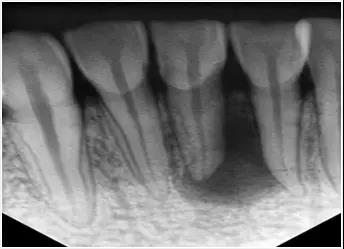

1、術前拍攝X線片

在

過程中,在杜牙根術前拍X線片,以幫助診斷,瞭解髓室的位置和根管數目及形態,測量根管工作長度及日後隨訪和評價療效提供對比的依據。

應用平行投照X線方法、根管長度測量儀確定根管度,最好插針拍X片。